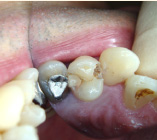

下の写真の一番左は実は治療前の写真です。痛みもなく一見問題なく入っている銀歯も除去してみると中に虫歯が。殺菌作用のある薬を詰めて治療中です。外からは分かりずらい虫歯も多いので定期検診がおすすめです。

- 治療前

- 除去

- 治療中